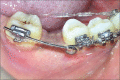

The interdisciplinary collaboration of periodontics and orthodontics has allowed teeth to be moved 2-3 times faster, reducing the time required for traditional orthodontic therapy considerably. Periodontally accelerated osteogenic orthodontics (PAOO), also known as Wilckodontics, is a combination of a selective decortication facilitated orthodontics and alveolar augmentation. With this technique, there is no dependence on the pre-existing alveolar volume. This case report describes the treatment of permanent mandibular molar protraction in a 14-year-old patient undergoing orthodontic therapy using PAOO with piezosurgery.